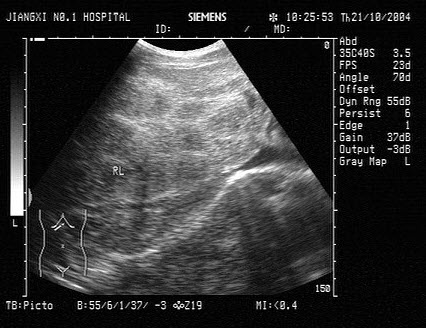

①折射系数